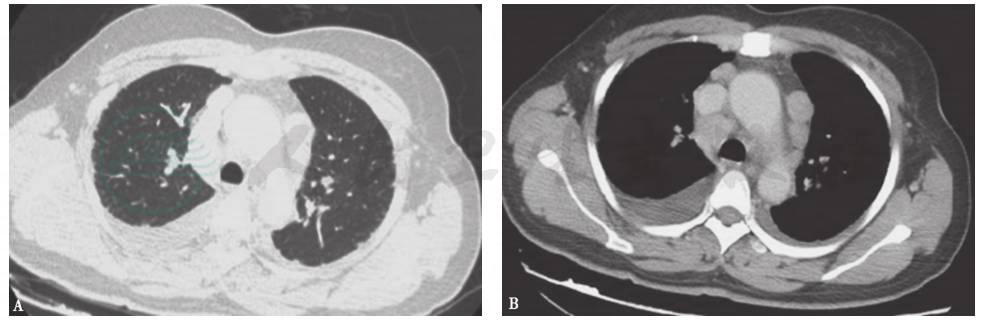

胸部CT:纵隔内见多组淋巴结肿大,斜裂胸膜区多发小结节影,双肺间质纹理增多,双侧胸腔积液,少量心包积液(图1)。

图1 胸部CT表现

胸部CT可见纵隔多组淋巴结肿大,双肺间质纹理增多,双侧胸腔积液,右侧胸腔积液更为明显